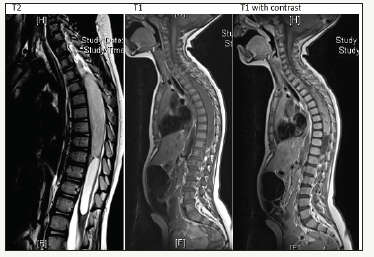

figure 1:MRI images showing an intramedullary tumor from T3-T9 with enhancement in T2-weight and contrast enhancement and accompanied with a syrinx.

Brain and whole spine magnetic resonance (MRI) were performed. Cranial MRI was normal, however the thoracic spine MRI with contrast administration revealed a 2x2x14 cm cystic mass with peripheral enhancement located at the level of T3-T9 vertebrae (Figure 1) The lesion caused an expansion of the cord. T2-weighted images showed hyperintensity consistent with vasogenic edema, the differential diagnose favored a diffuse astrocytoma grade II.